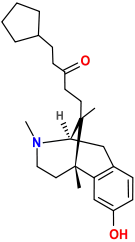

Benzomorphans

- 5,9 alpha-diethyl-2-hydroxybenzomorphan (5,9-DEHB)

- 8-Carboxamidocyclazocine (8-CAC)

- Alazocine

- Anazocine

- Bremazocine

- Butinazocine

- Carbazocine

- Cogazocine

- Cyclazocine

- Dezocine

- Eptazocine

- Etazocine

- Ethylketazocine

- Fedotozine

- Fluorophen

- Gemazocine

- Ibazocine

- Ketazocine

- Metazocine

- Moxazocine

- Pentazocine

- Phenazocine

- Quadazocine

- SKF-10047

Structures

| Benzomorphans | ||||

|---|---|---|---|---|

5,9 alpha-diethyl-2-hydroxybenzomorphan 5,9 alpha-diethyl-2-hydroxybenzomorphan (5,9-DEHB) |

8-Carboxamidocyclazocine 8-Carboxamidocyclazocine |

Alazocine Alazocine |

Anazocine Anazocine |

Bremazocine Bremazocine |

Butinazocine Butinazocine |

Carbazocine Carbazocine |

Cogazocine Cogazocine |

Cyclazocine Cyclazocine |

Dezocine Dezocine |

Eptazocine Eptazocine |

Etazocine Etazocine |

Ethylketocyclazocine Ethylketocyclazocine |

Fedotozine Fedotozine |

Fluorophen Fluorophen |

Gemazocine Gemazocine |

Ibazocine Ibazocine |

Ketazocine Ketazocine |

Metazocine Metazocine |

Moxazocine Moxazocine |

Pentazocine Pentazocine |

Phenazocine Phenazocine |

Quadazocine Quadazocine

|

Thiazocine Thiazocine |

Tonazocine Tonazocine |

Volazocine Volazocine |

Zenazocine Zenazocine |

|||